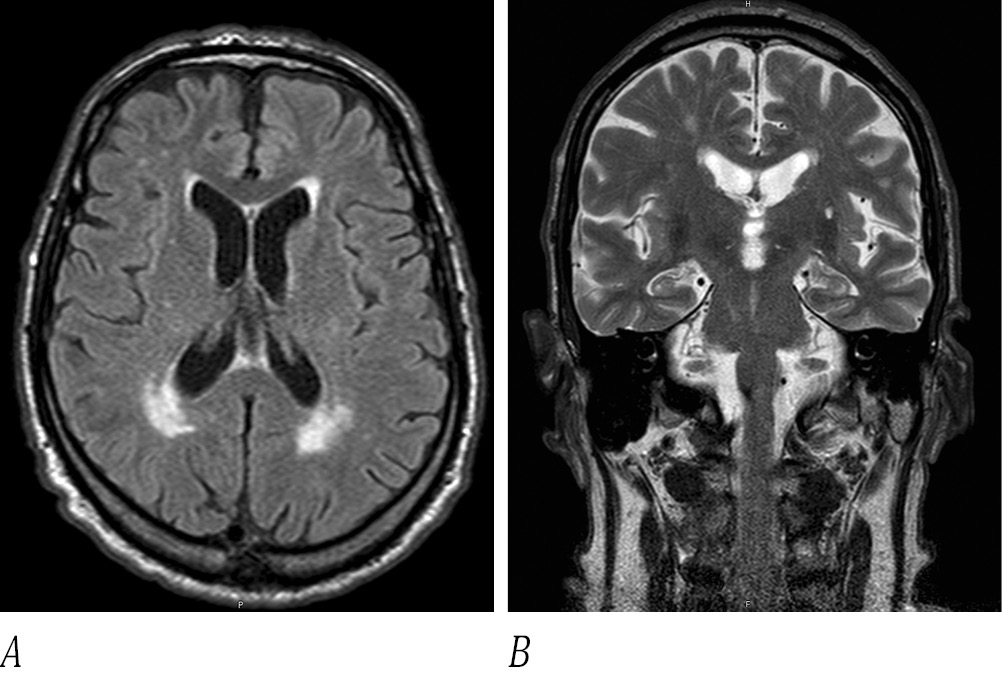

Для исключения очаговой патологии области ствола головного мозга проведено МРТ. Выявлены признаки хронической цереброваскулярной недостаточности (рис. 3).

Рис. 3. МРТ головного мозга пациента Н. в режимах Т2 (A) и FLAIR (B) c перивентрикулярными очагами гиперинтенсивного сигнала сосудистого генеза.

Fig. 3. Periventricular hyperintensity of vascular origin on T2 (A) and FLAIR (B) MRI scans of the patient's brain.